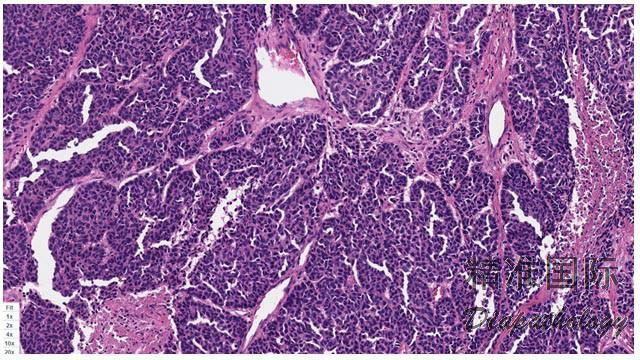

肺基底样鳞状细胞癌

Lung Basaloid Squamous Cell Carcinoma

是一种分化较差的上皮性肿瘤,由小细胞增生形成小叶状结构,周边呈栅栏状排列,可伴有角化型或非角化型鳞癌成分,但基底样细胞成分>50%。

实性结节状或相互连通的梁状浸润性生长;

癌巢周围肿瘤细胞核呈栅栏状排列;

肿瘤细胞相对较小,形态一致,立方形或短梭形,染色质中等,细颗粒状或泡状,核仁小或无;胞浆稀少,但界限清楚;

核分裂像多见,(15-50 个/2mm2);

缺乏渐进性角化,但可能存在角化珠;

部分病例可见粉刺样坏死;

7.1/3 的病例可见菊型团;

多数病例具有玻璃样变或黏液性间质;